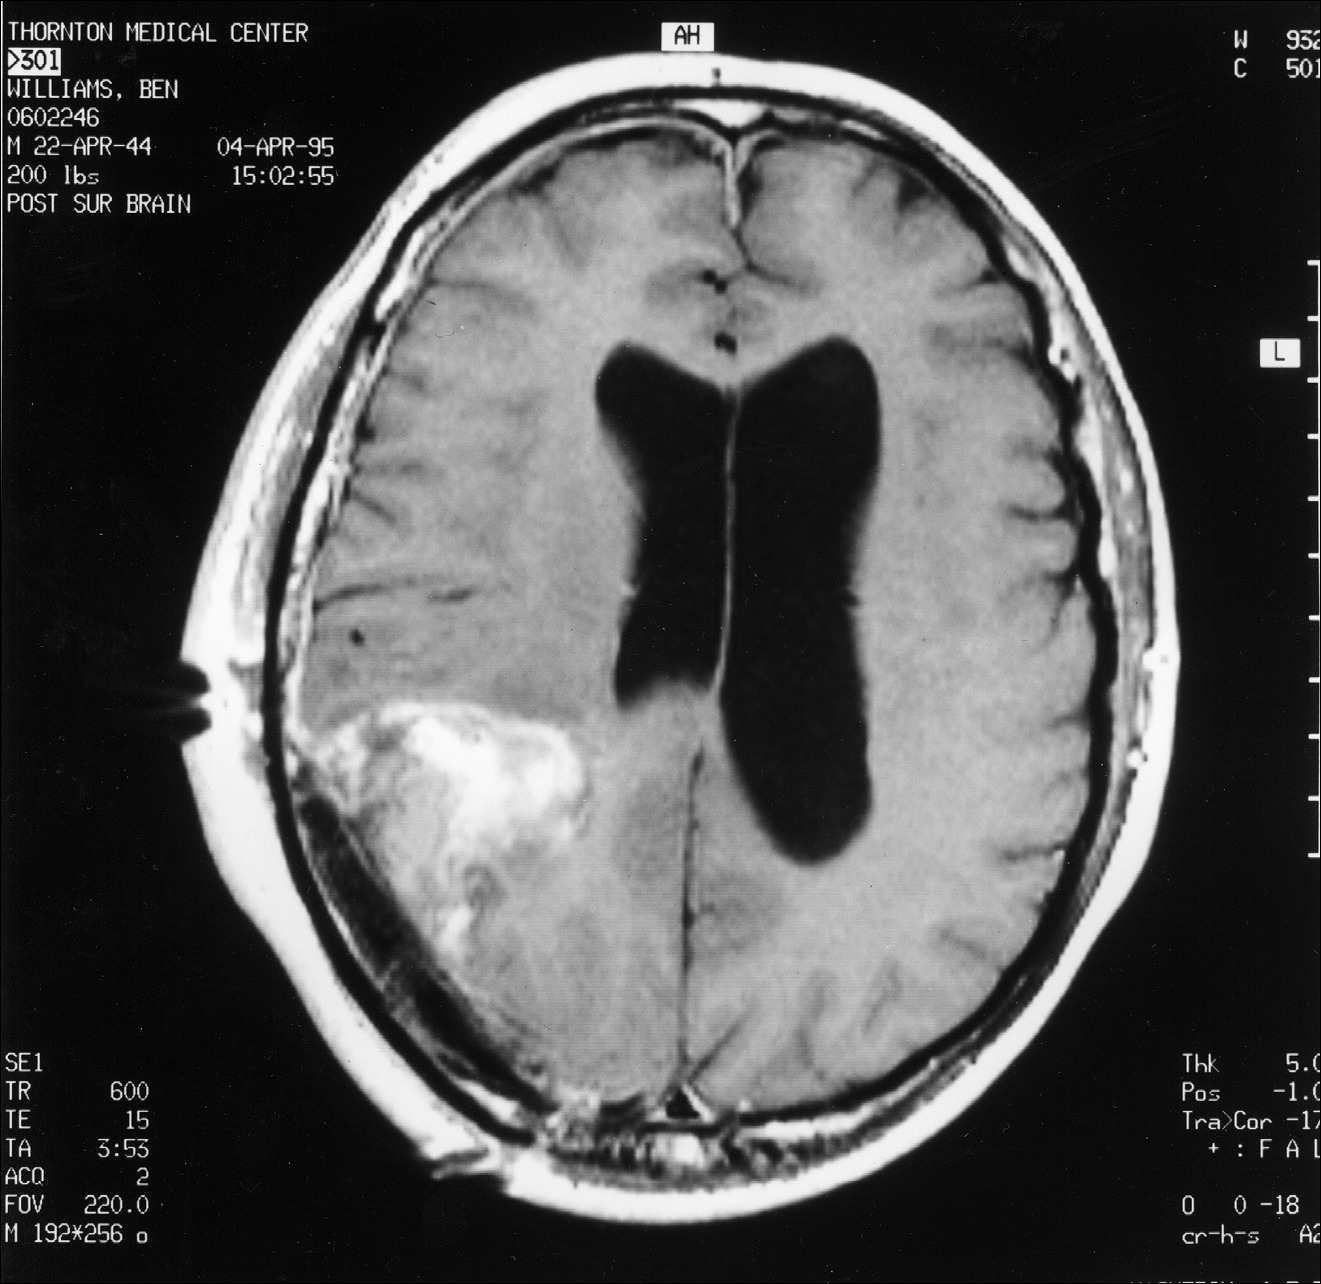

Kitą rytą su Diane susitikome su dr. Marshall aptarti MRT rezultatų. Jis paaiškino, kad stengėsi pašalinti visą matomą naviką, tačiau toli už jo ribų nėjo. Navikas buvo toks didelis, kad papildomas šalinimas būtų sukėlęs rimtų mano regėjimo problemų. Gliomos tipo smegenų navikai turi mikroskopinius ūselius, besitęsiančius du–tris centimetrus už matomų naviko ribų, todėl pašalinti visas naviko ląsteles yra nepaprastai sunku. Tik patys agresyviausi neurochirurgai sugeba pašalinti šiuos nematomus ūselius, dažnai sukeldami reikšmingą paciento funkcinį pablogėjimą. Kadangi dr. Marshall operavo konservatyviau, mano MRT parodė, kad liko nemaža naviko dalis (žr. čia ir čia). Dr. Marshall neatrodė ypač susirūpinęs dėl likusio naviko ir paminėjo, kad jo kolega dr. David Barba galėtų jį veiksmingai gydyti spindulinės terapijos implantu, vadinamu brachiterapija. Tuo metu neturėjau supratimo, apie ką jis kalba. Mano mintis užvaldė tai, kad po operacijos liko nemaža naviko dalis.

3 pav.

Pooperacinis MRT pjūvis, atliktas per smegenų vidurį tarp priekio ir galo.

4 pav.

Pooperacinis MRT pjūvis, atliktas per smegenų vidurį tarp viršaus ir apačios. Abu pjūviai rodo, kad po operacijos liko nemaža naviko dalis.